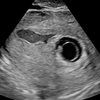

私の場合、D3エコーで遺残卵胞もなかったし、月経周期が乱れてるわけでもないのになぜ治療はじめられなかったんだろう…。